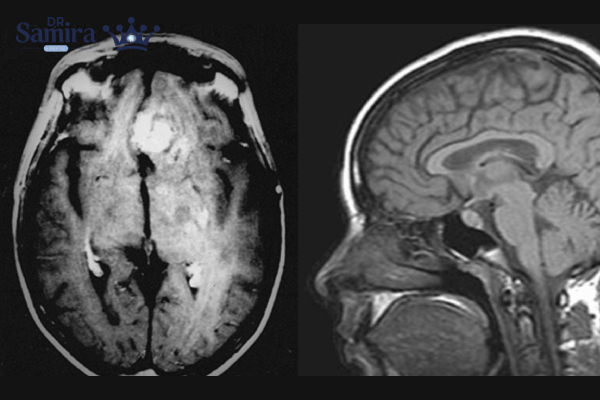

تومورهای سلولهای زاینده زمانی شکل میگیرند که سلولهایی که در دوران جنینی باید به سمت اندامهای جنسی حرکت کنند، در مغز باقی بمانند و بعد از سالها فعالیت غیرطبیعی پیدا کنند. به همین دلیل، این تومورها در نواحی پینه آل (غده صنوبری) و سوپراسلار دیده میشوند. این تومورها حدود ۱ تا ۳ درصد کل تومورهای مغزی را تشکیل میدهند، اما در کودکان و نوجوانان میزان بیشتری دارند.

تومورهای سلولهای زاینده مغزی، چه ژرمینوما و چه نانژرمینوما، علاوه بر رشد خود تومور، میتوانند به ساختارهای حیاتی مغز فشار وارد کنند و عملکرد طبیعی آنها را دچار اختلال کنند. از آنجا که این تومورها معمولاً در مراکز حساسی مثل ناحیه پینهآل و سوپراسلار ایجاد میشوند، هر نوع رشد اضافی میتواند با پیامدهای عصبی، هورمونی و بینایی همراه باشد. شدت عوارض بستگی دارد به نوع تومور، سرعت رشد، محل قرارگیری و میزان انتشار آن.